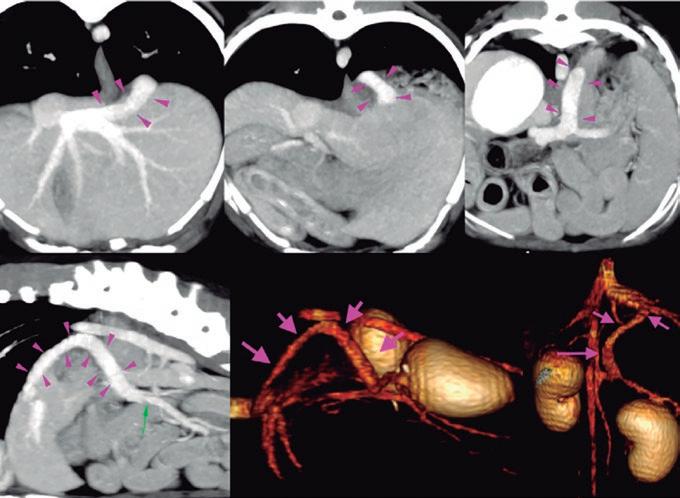

La radiología intervencionista es una especialidad que se encarga del diagnóstico y tratamiento de una gran cantidad de patologías de una forma mínimamente invasiva. Para realizar estos procedimientos es imprescindible disponer del equipamiento adecuado, tener nociones tanto de la instrumentalización como de las diferentes técnicas, y conocer con precisión la anatomía del paciente. Se trata de técnicas cada vez más implementadas en la clínica diaria ya que permiten solucionar diferentes patologías con una menor agresión a nivel tisular, una rápida recuperación, son procedimientos sin dolor, rápidos y seguros, suponen un menor coste respecto a otras cirugías invasivas, y constituyen una alternativa terapéutica a pacientes que no se pueden operar de forma convencional. Entre las más frecuentes destaca el cierre del conducto arterioso persistente, valvuloplastias en estenosis pulmonar, oclusión de shunts portosistémicos, implantación de marcapasos y colocación de stents

La radiología intervencionista, también conocida como radiología vascular e intervencionista, es una especialidad que se encarga del diagnóstico y tratamiento de una gran cantidad de enfermedades de una manera mínimamente invasiva. Se realiza mediante un abordaje guiado por distintas técnicas de imagen como, por ejemplo, la ecografía, la fluoroscopia o la tomografía computarizada, para alcanzar la zona a diagnosticar o tratar.

La radiología vascular e intervencionista ofrece una alternativa segura y eficaz a la cirugía en muchas enfermedades. Entre sus ventajas para el paciente destaca una menor agresión a nivel tisular, una rápida recuperación, procedimientos sin dolor, rápidos y seguros, un menor coste respecto a otras muchas cirugías con mis-

imágenes basadas en rayos X y posteriormente las convierte en una señal de vídeo en tiempo real. Estas imágenes pueden manipularse ofreciendo funciones como la angiografía de sustracción digital, mapeo vascular y ampliación. Respecto a una radiografía, la exposición de rayos X necesaria para realizar una fluoroscopia es baja, pero debido a la duración de las series de imágenes que habitualmente se toman, el nivel de exposición en los pacientes suele ser elevado. Por lo tanto, es importante controlar el tiempo de exposición y llevar un registro de este. El fluoroscopio debe estar situado en una sala adecuada para su uso seguro, y todo el personal que entre en la sala de fluoroscopia debe protegerse de la radiación utilizando un delantal plomado, protectores de tiroides y gafas plomadas.